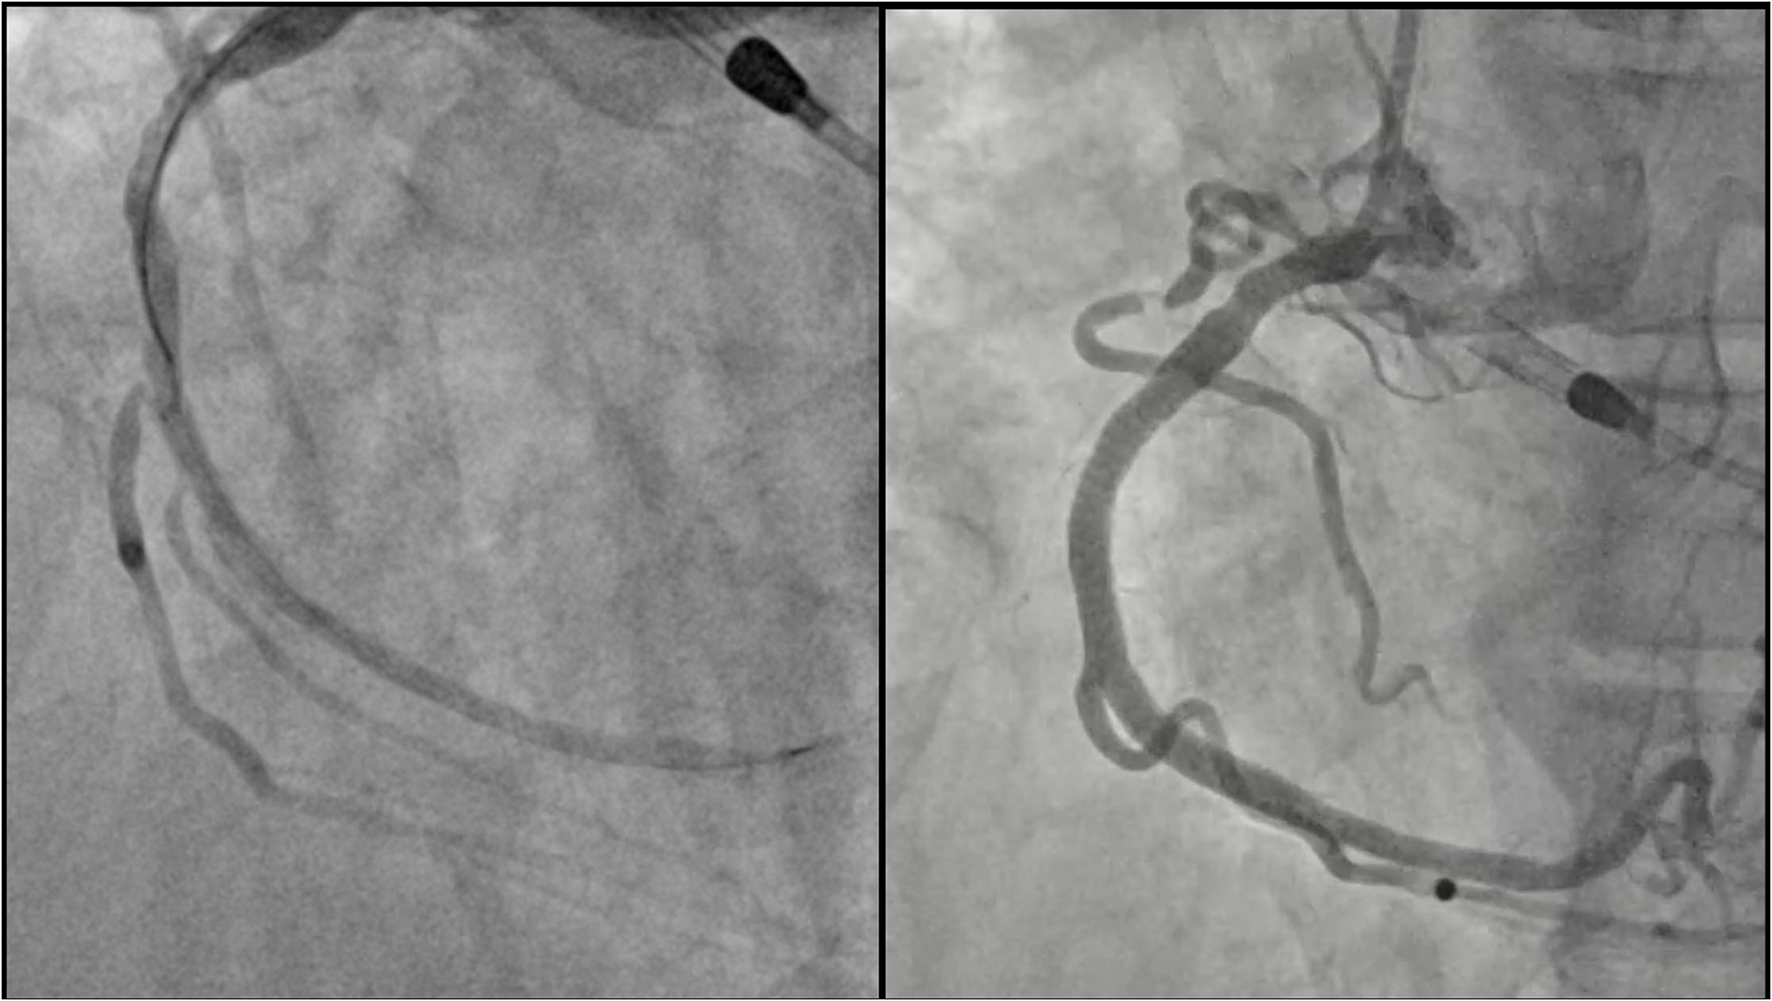

Figure 3

Left circumflex coronary artery after PCI. Final result after implantation of two drug-eluting stents using the T-stent technique.

Figure 4

Right coronary artery after PCI. Left panel: result after predilatation. A severe stenosis of the marginal branch ostium is shown. Note the Supercross 120° microcatheter that was used to wire the branch. Right panel: final result after deployment of the Tryton side branch stent in the marginal branch and multiple drug-eluting stent implantation in the right coronary artery.